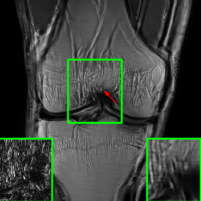

Figure 10 presents visual comparison of image reconstructions and their associated reconstruction errors within a closely examined region. Each image in the figure includes two inset panels in the bottom-left and bottom-right corners. The bottom-left inset panel, enclosed within a green bounding box, serves as a reference for the region of interest in the image. In contrast, the bottom-right inset panel depicts an error map in relation to the ground truth. Notably, our method stands out in its ability to capture more features from the original image, surpassing the performance of alternative methods (as also evident from the reported PSNR values).